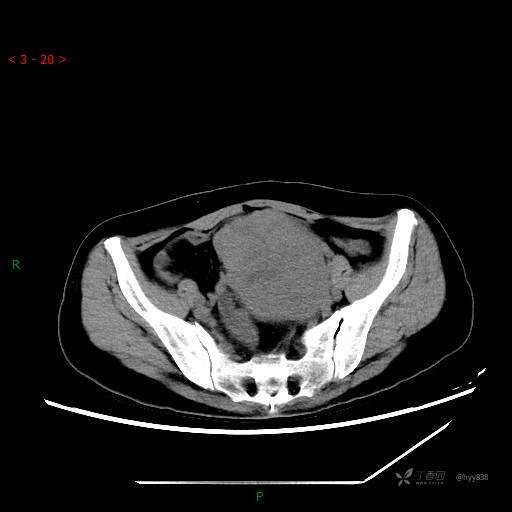

辅助检查:CT

盆腔CT平扫